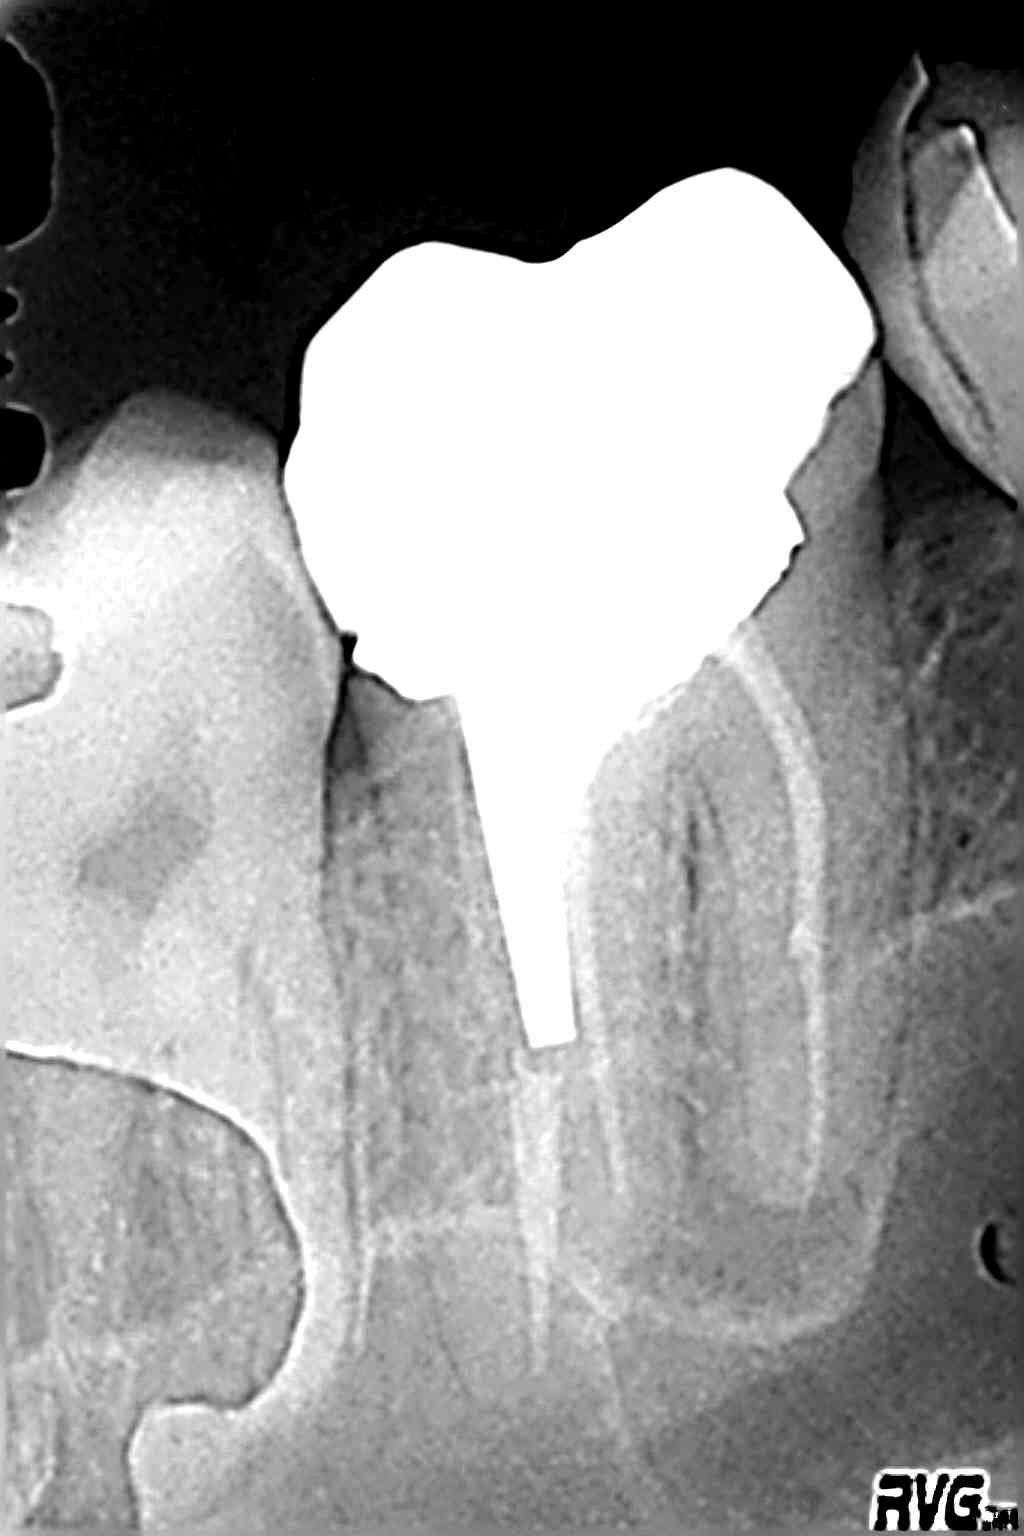

le nombre de fois où le CBCT nous montre des lésion interradiculaires non visibles sur les rétros ...

Ci-joint sur une reprise de traitement, où le cone Beam révélait une fenêtre vestibulaire et un plancher absent, et un mv2 absent.

- échec pour trouver le MV2, étiologie la plus probable de la douleur.... pourquoi pas un CBCT pour valider la presence et la morphologie du MV2 (voire d'un MV3), la presence ou pas d'une lésion apicale (en supposant qu'il ait un plafond osseux et non pas juste la membrane coiffant l'apex).la presence ou pas d'une fenestration de la paroi alvéolaire en V à hauteur de la zone apicale (irritation par le dépassement)